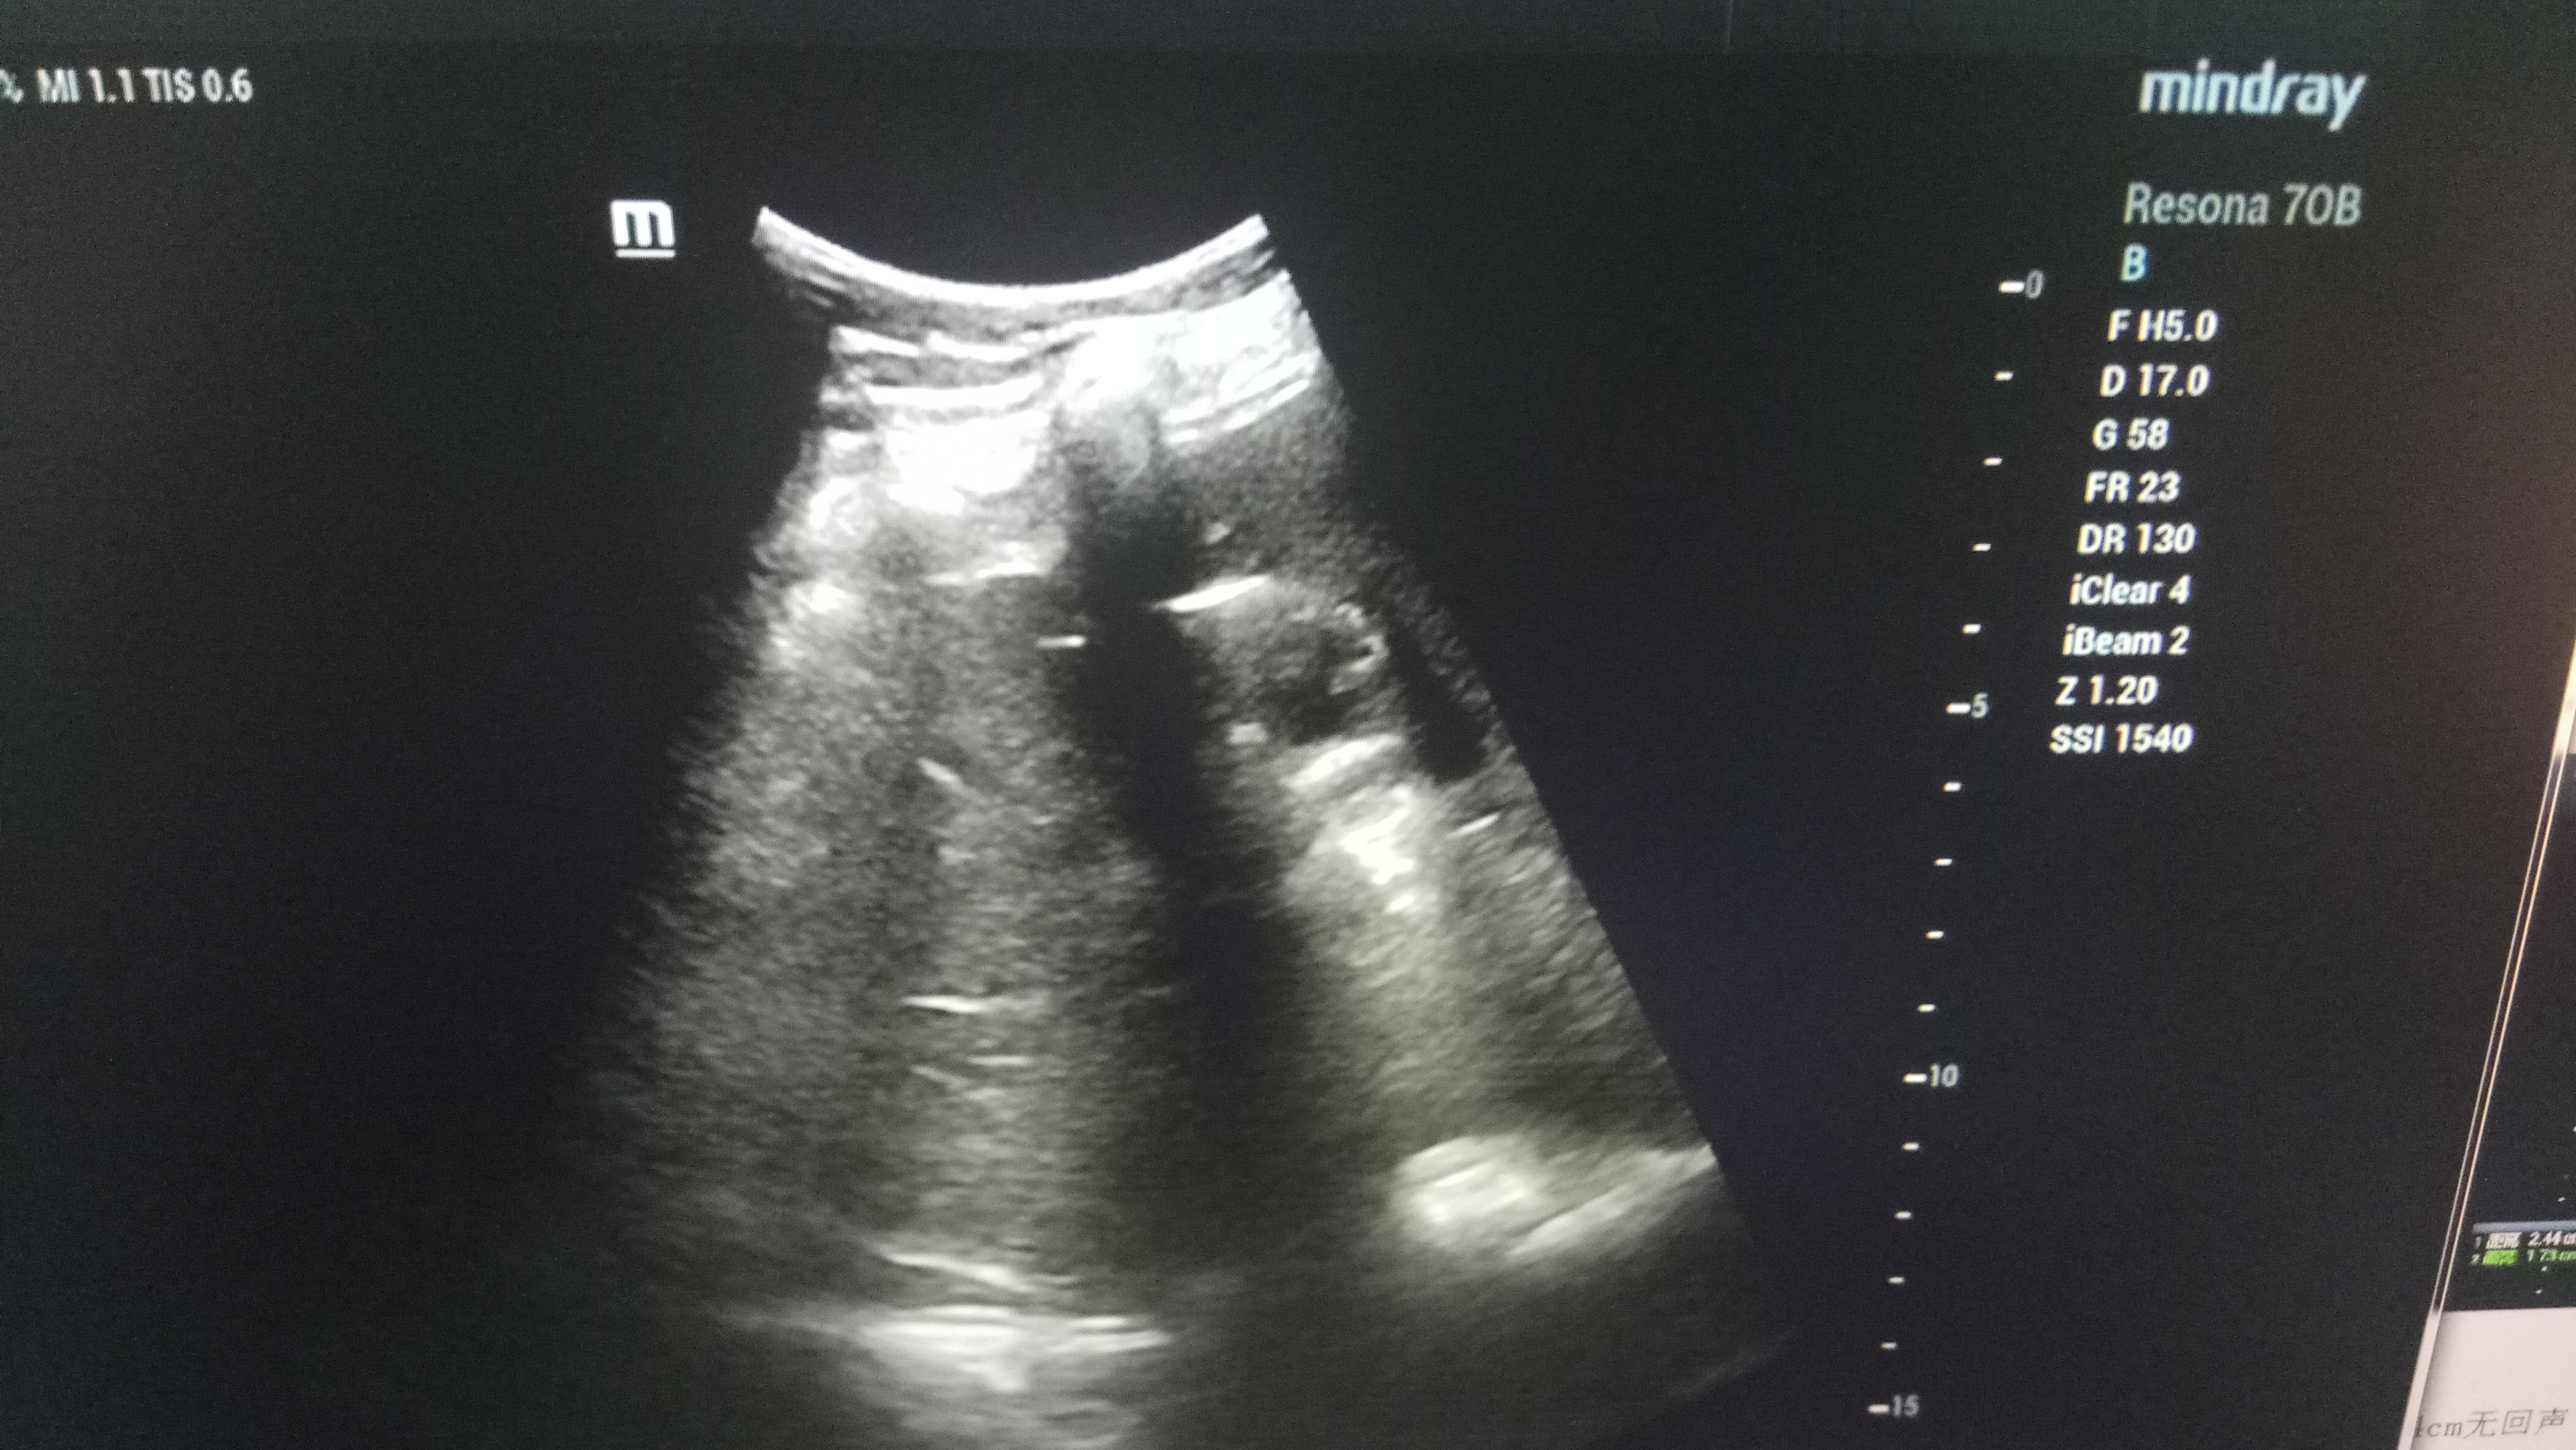

近日,成人导航 超声科在高陵区成人导航 成功开展了一例超声引导下肝囊肿抽吸硬化治疗术。患者前段时间查出肝囊肿,因开腹手术风险性大且痛苦,遂联系了高陵区成人导航 超声科,在成人导航 超声科主任展小军与对口支援医生杨艳秋的紧密配合下,短短30分钟,通过一根穿刺针,直径近7cm的肝囊肿就被完全抽吸硬化完毕,患者生命体征平稳,休息几小时后已活动自如。

超声介入微创诊疗技术是在实时超声的监视和引导下,完成各种穿刺、活检以及抽吸、插管、注药治疗等操作,达到与外科手术相当的效果,具有创伤小、恢复快、无辐射、介入治疗定位精确等优点。可治疗全身各部位囊肿,尤其是巧克力囊肿效果更佳,还有全身各部位肿瘤的活检和治疗,超声引导下微创治疗是未来医学发展方向。